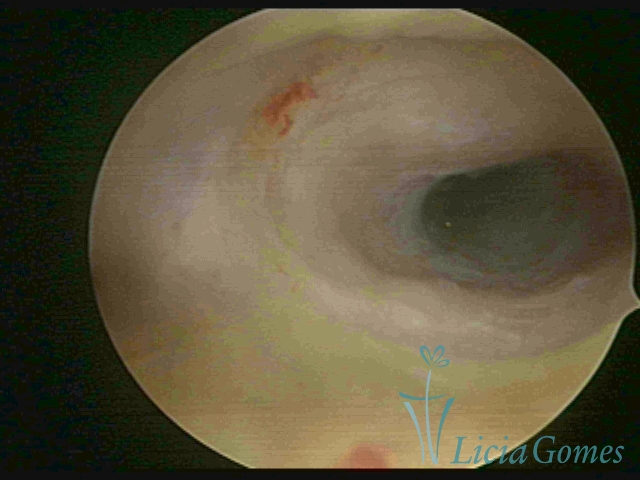

Terceira porção ou porção superior

Apresenta a mucosa com a superfície lisa e pouco vascularizada até a altura do orifício interno